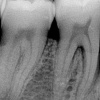

Agressiivse parodontiidi kahjustused rasedal naispatsiendil